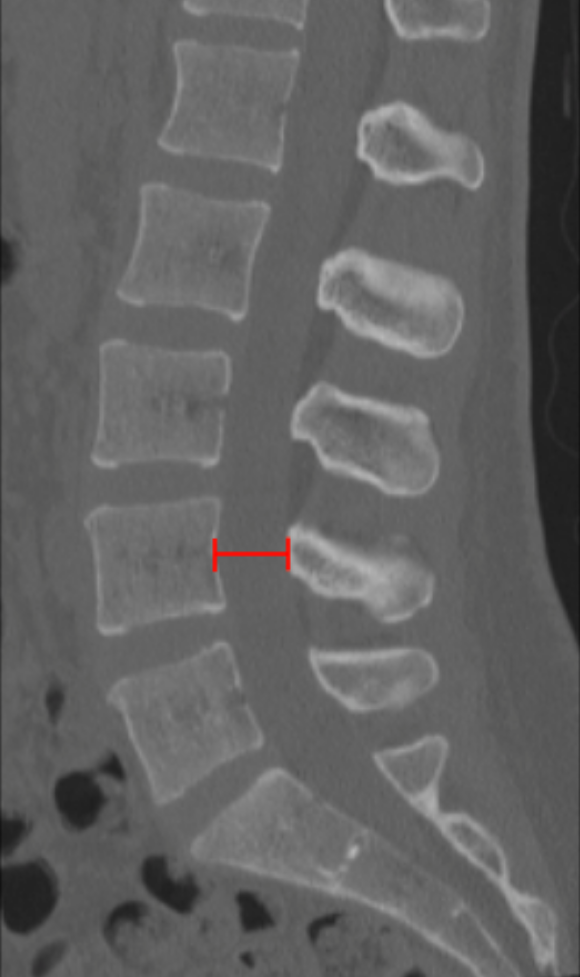

Anteroposterior (AP) Canal Diameter

Lumbar AP canal diameter on CT quantifies the anteroposterior bony dimension of the spinal canal and is a classic metric for diagnosing developmental or degenerative lumbar spinal stenosis. It reflects the space available for the thecal sac and cauda equina and is particularly useful when MRI is unavailable or contraindicated.

• Identify the lumbar level of maximal canal narrowing on sagittal CT.

• Scroll to the corresponding axial CT slice at the mid-vertebral body or disc level.

• Identify:

• Posterior vertebral body cortex (anterior boundary), and

• Anterior cortex of the lamina / base of the spinous process (posterior boundary).

• Draw a straight line between these two points along the midline of the spinal canal.

• Record the distance in millimeters (mm) — this is the AP canal diameter.

• Normal AP diameter: > 12 mm

• Relative stenosis: 10-12 mm

• Absolute stenosis: < 10 mm

• Critical stenosis: < 7 mm

Symptoms of neurogenic claudication are most likely when diameter is < 10 mm.